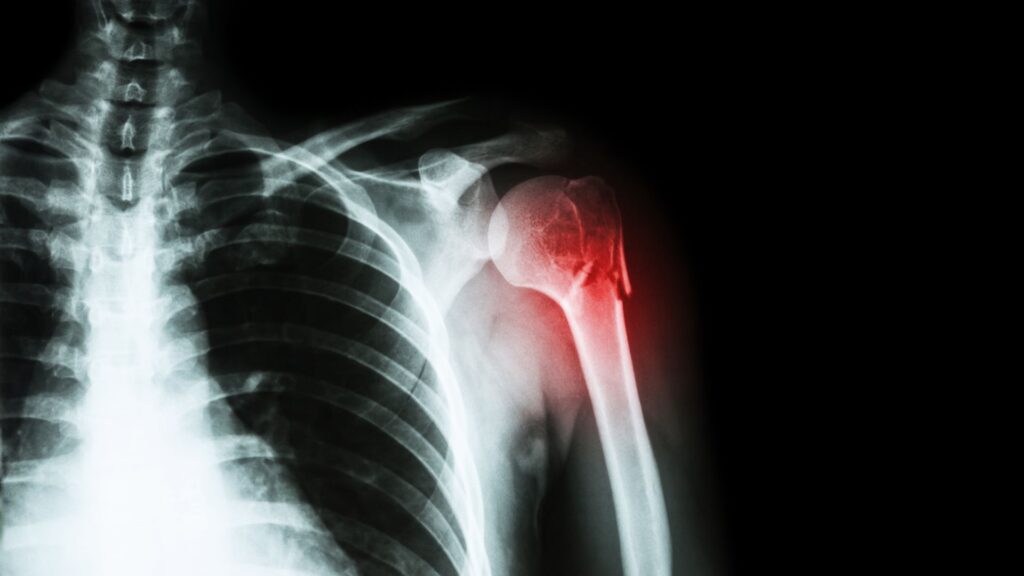

② 高齢期の「骨折リスク」

60歳を超えると、転倒などによる骨折の頻度が急増します。入院だけでなく、その後の生活サポートにも費用がかかります。

私の父は60代後半で一度入院しましたが、幸いにも大事には至りませんでした。ただ、その時最も心配したのは「骨折」でした。地方在住でもあり、自宅での生活支援やリハビリの費用は、年金収入だけでは心もとないのです。

1. 高齢者リスクの決定版!手厚い「骨折見舞金」を標準搭載

入院保障に加えて、骨折見舞金が付帯。例えば入院日額10,000円プランなら3万円が給付されます。